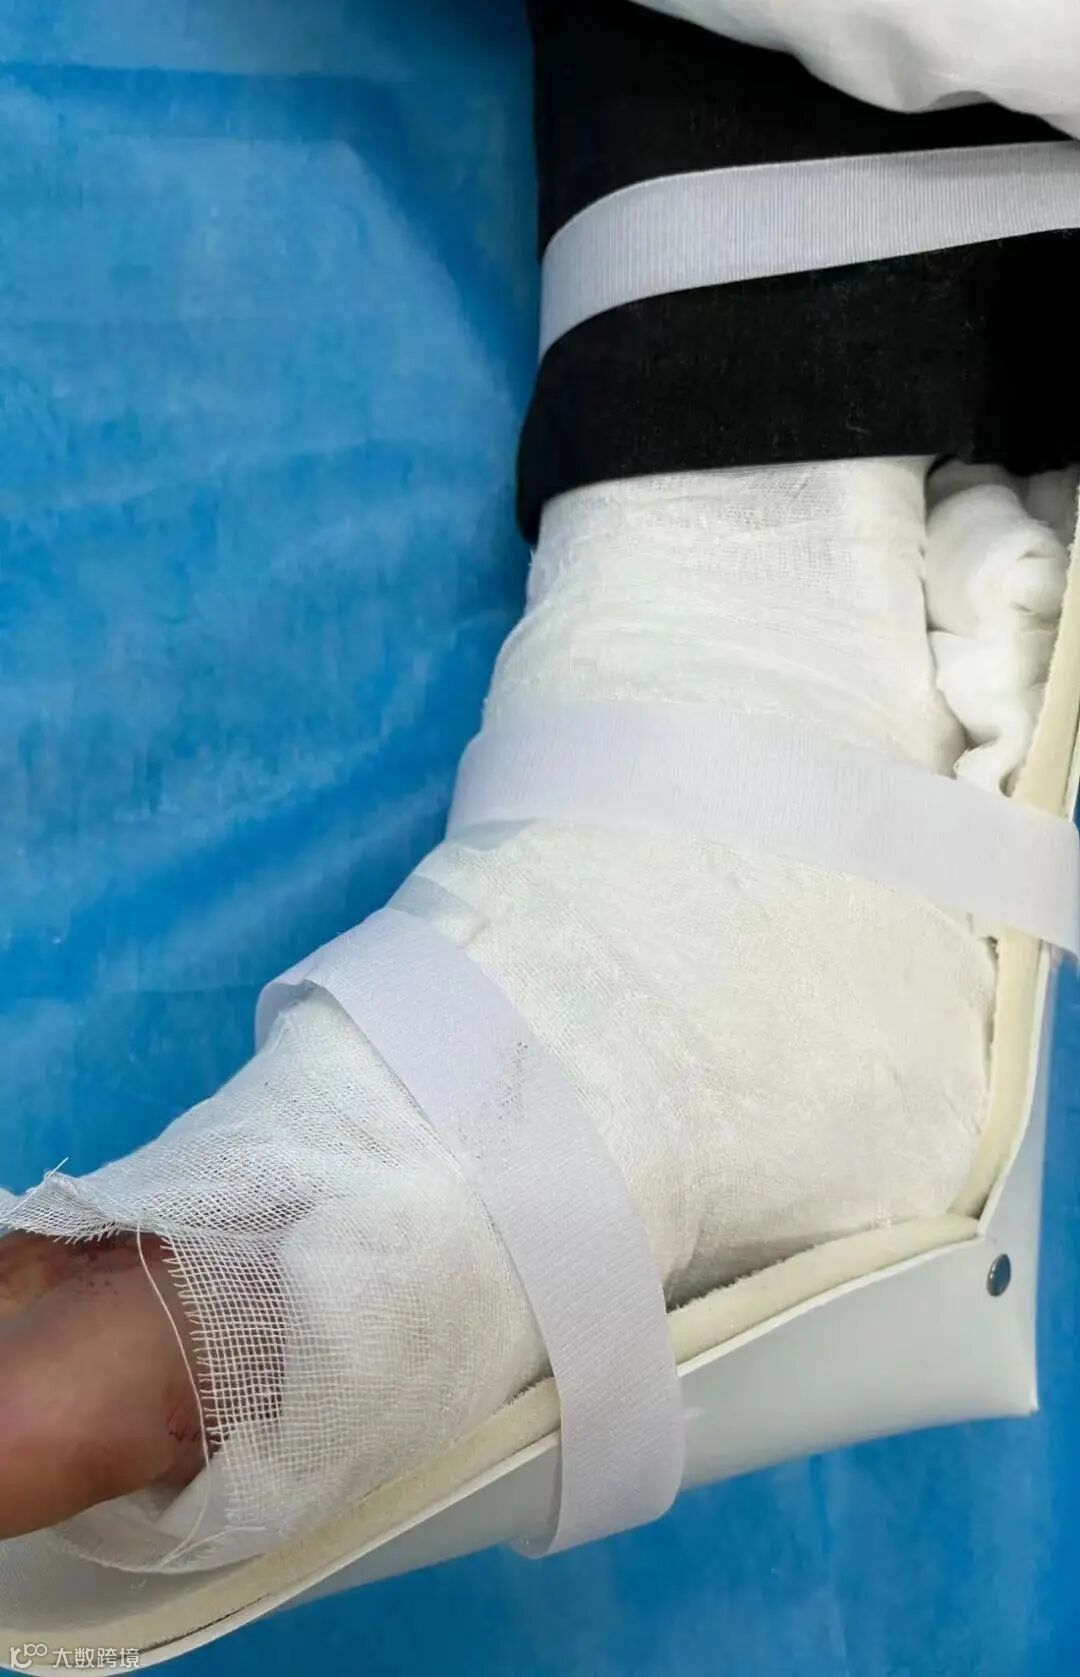

外科韦成业医师主刀手术,术中查找到4处直径约1毫米动脉喷血点,马上结扎止血,术中可见并处理2粒直径约1毫米碎骨,仔细检查可见被切的骨骼肌肌腱和肌腹大部分呈纵向,术中对受伤跟腱、肌腱和肌腹做修复处理,对切缘各层仔细分层对齐缝合,经过近1小时手术,终于成功结扎止血缝合切口。

手术成功后,出血几乎停止,加上及时有效补充血容量,陈叔病情明显好转,肢端血运良好,运动功能基本恢复,手脚回暖,脸色逐步红润,精神状态逐步恢复,血压回升到正常,转危为安。